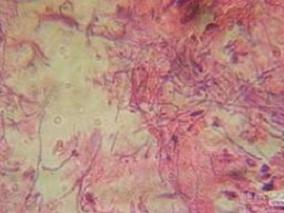

1小时条评论患者,男性,35岁,广东人。 主诉:反复乏力、食欲缺乏16年,下肢皮肤溃疡1月余。 现病史:患者于16年前开始出现反复乏力、食欲缺乏,于外院确诊慢性肾小球肾炎、慢性肾衰竭(尿毒症期),血液透析数次后于广州某医院行同种异体肾移植术,术后出现急性排斥反应给予...